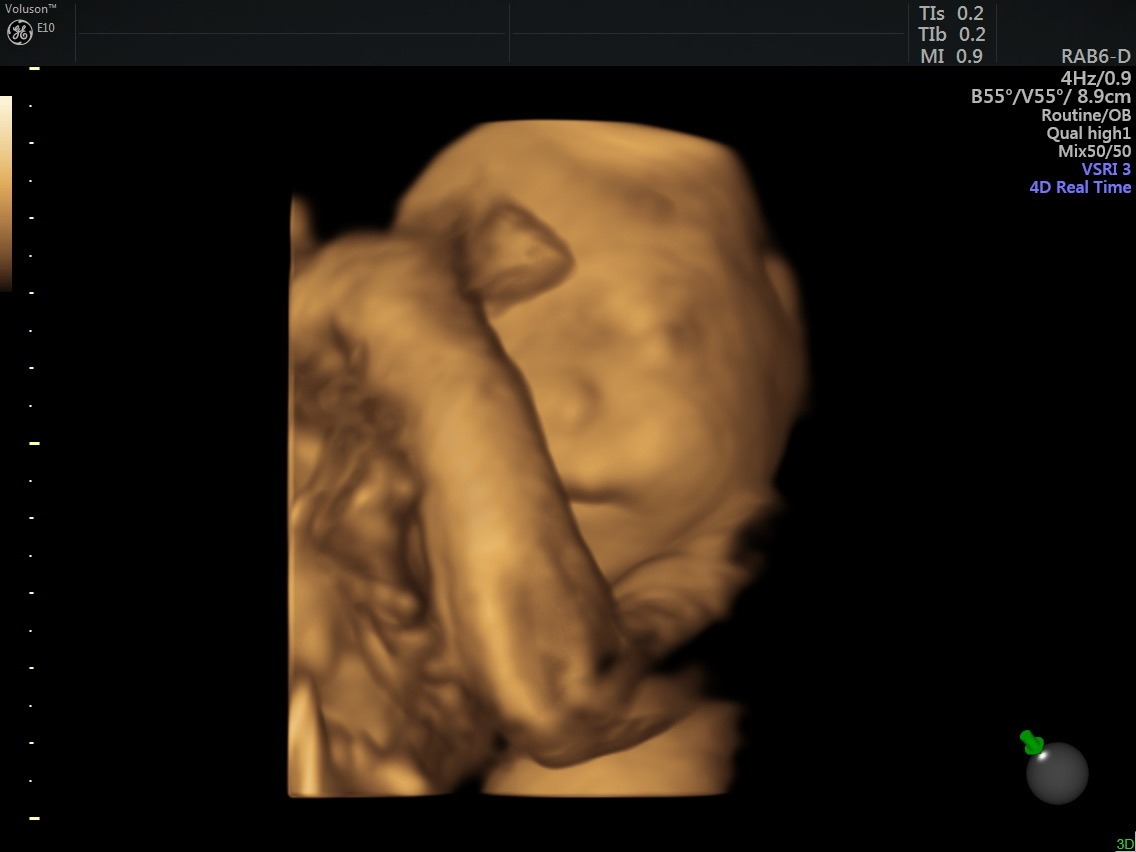

Recently, they received the news that sweet baby Dottie has been diagnosed with a cleft palate. While this condition is treatable, it will require multiple surgeries, specialized medical care, and ongoing follow-up appointments after she is born.